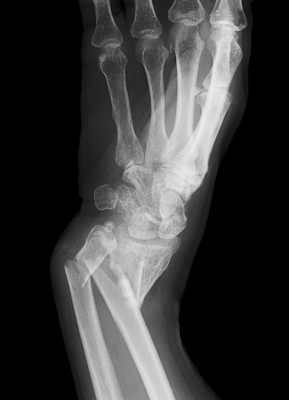

Fracturile se produc pe neasteptate, fara a ocoli pe nimeni iar frecventa lor creste mai ales iarna. Fracturile sunt definite ca o intrerupere a continuitatii unui os rezultata in urma unui traumatism sau a unei suprasolicitari.

- radiografia standard: permite in majoritatea cazurilor stabilirea unui diagnostic exact. Aceasta se efectueaza in doua incidente care vor avea intre ele un unghi de 90? (fata si profil). In unele cazuri pot fi necesare efectuarea unor radiografii cu incidente speciale;